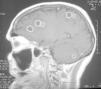

Mujer de 60 años con uveítis crónica en tratamiento con corticoides. Ingresa por cuadro de tres días con cefalea, vómitos y fiebre, disminución del nivel de conciencia y disfasia. Al ingreso presentaba una temperatura de 39 ºC, crisis tónico clónicas y flúter auricular con hipotensión. Se intubó y conectó a ventilación mecánica. Se le realizó tomografía computarizada craneal con contraste y resonancia magnética donde se ven múltiples lesiones en ambos hemisferios cerebrales y en el cerebelo con captación en anillo (figs. 1 y 2) y edema asociado, que brillan en difusión, compatibles con abscesos piógenos. No se aisló ningún germen en sangre, orina, aspirado traqueal ni líquido cefalorraquídeo. Se realizaron estudios para encontrar el foco de la infección, exploraciones del área otorrinolaringológica, fondo de ojo, ecocardiografía transesofágica, etc., siendo todos normales. Tras tratamiento con meropenem la paciente evolucionó favorablemente, siendo dada de alta asintomática al Servicio de Neurología.